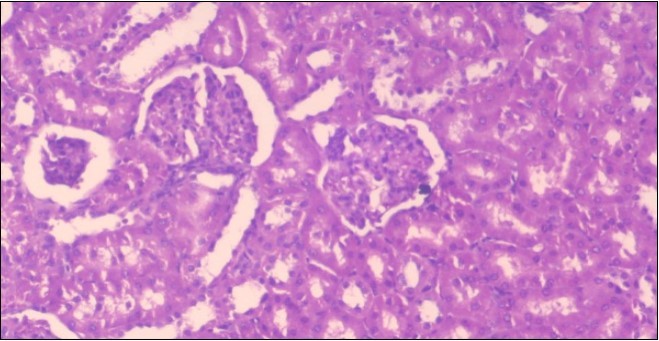

The histological examination of the kidney of the control rats fed on a standard diet showing normal rounded capsules with normal Bowman's glomeruli, round proximal tubules and elongated distal tubules with high cuboidal cells figure 1. The rats fed (HFD) showed fatty degeneration of the tubules with eosinophilic material deposition, glomerular atrophy with wide urinary space and distal tubules with extrusion of nuclei into lumen figure 2. By comparison kidneys of rats which were treated by fennel after being obese and the control rats observed partial improvement in both Bowman's capsules and proximal tubules. Note the distal tubules show less focal fatty infiltration figure 3.While examination of rats kidney that were treated by ator after obesity showed improvement in Bowman's capsules with normal glomerular and partial improvement in proximal tubules and distal tubules, figure 4. Kidney of rats that were treated by fennel and ator after obesity and the control rats showed high improvement in the tissues with normal glomerular and that Most of Bowman's capsules and renal tubules, restoring their normal appearance figure 5.

Figure 1.Photomicrogragh of kidney section of control rat showing normal rounded capsules with normal Bowman,s glomeruli, round proximal tubules and elongated distal tubules with high cuboidal cells , (H&E) (40X).

Figure 2.Photomicrogragh of kidney section of obese rat showing fatty degeneration of the tubules with eosinophilic matrial deposition, glomrerular atrophy with wide urinary space and distal tubules with extrusion of nuclei into lumen , (H&E) (40X).